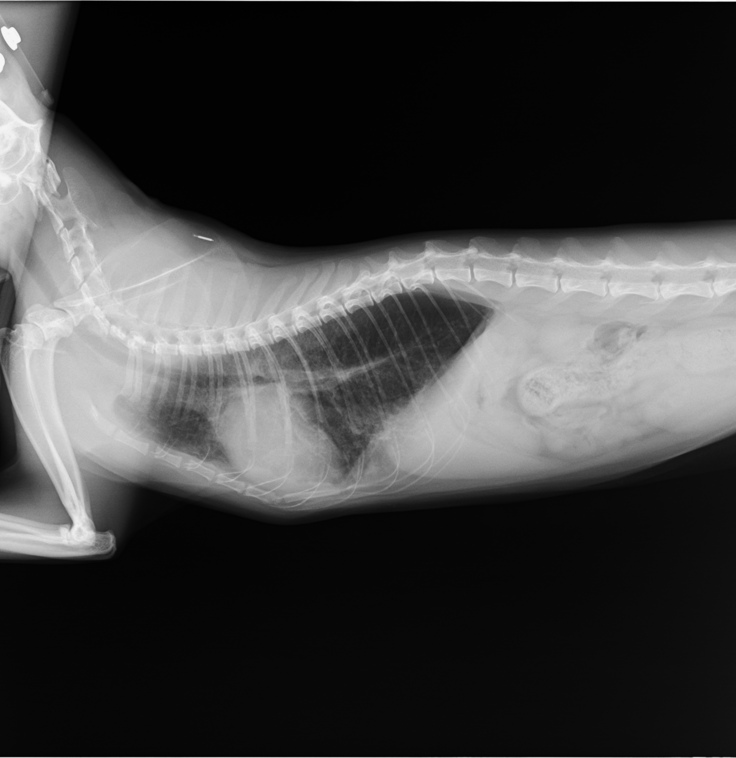

2021年9月

再び、咳の症状が出てきてきたので病院へ行きました。

その時のレントゲン写真です。

2019年のものと比べると、明らかに心臓の上部が肥大し、

位置も体の中央によっています。

ここで肥大型心筋症と診断されました。

そして、治ったと思っていた気管支炎も、まだ完治しておらず

肺がまだ若干白いままです。